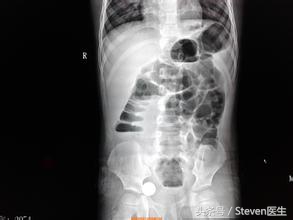

(2)辅助检查:X线立位腹平片检查:梗阻发生后的4~6小时,腹平片上即可见胀气的肠袢及多数气液平面。如立位腹平片表现为一位置固定的咖啡豆样积气影,应警惕有肠绞窄的存在;腹部CT对于发现腹部肠管扩张情况、腹水情况及肠管血供情况非常重要,必要时建议检查。

(2)辅助检查:X线立位腹平片表现为固定孤立的肠襻,呈咖啡豆状,假肿瘤状及花瓣状,且肠间隙增宽;腹部CT检查可看到腹腔内固定孤立肠襻,扩张肠管肠壁缺血、腹腔积液等,肠扭转的患者还可以看到肠系膜血管的“漩涡征”,CT检查对于发现梗阻的病因有较大意义。